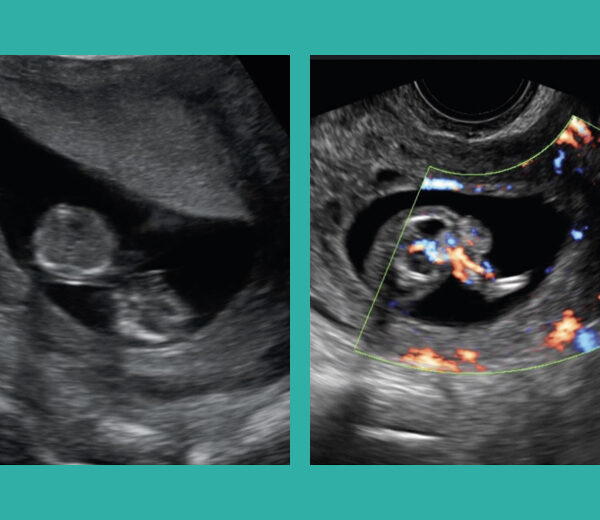

Caso clínico: Terapia láser intrafetal para la secuencia perfusión arterial inversa en gemelos

Una primigesta de 41 años con gestación doble monocoriónica bi amniótica, con diagnóstico ... Read More